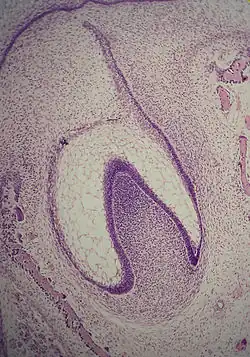

A: enamel organ

B: dental papilla

C: dental follicle

The tooth germ is an aggregation of cells that eventually forms a tooth.[2] These cells are derived from the ectoderm of the first pharyngeal arch and the ectomesenchyme of the neural crest.[1][3][4] The tooth germ is organized into three parts: the enamel organ, the dental papilla and the dental sac or follicle.